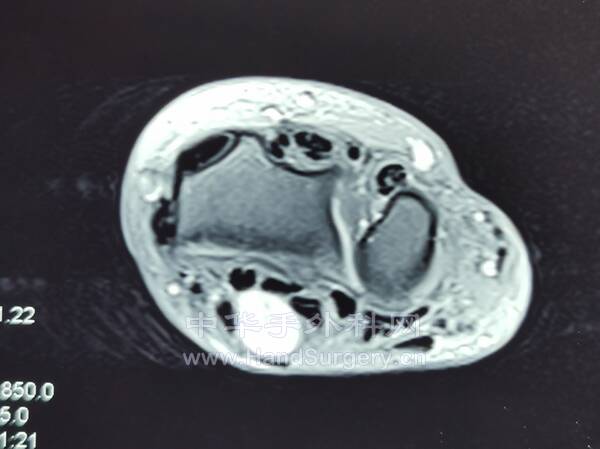

腱鞘巨细胞瘤(黄色素瘤)

沿郎格氏线设计切口